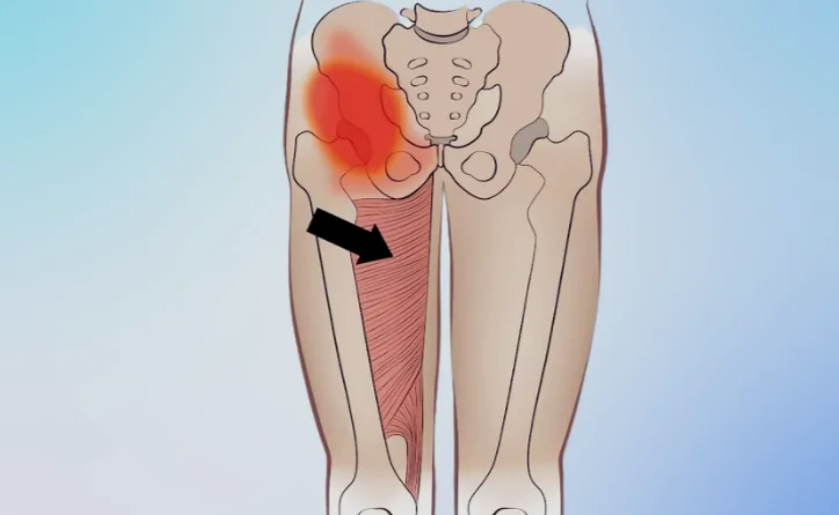

The groin region contains several muscles, but the most commonly affected are the adductor longus, adductor brevis, adductor magnus, gracilis, and pectineus. These muscles help bring the legs toward the center of the body and stabilize the pelvis during movement. Everyday actions like stepping sideways, climbing stairs, or maintaining balance on one leg rely heavily on these muscle groups.

When these muscles are overstretched or overloaded, small tears can develop in the muscle fibers. Depending on severity, strains are categorized into mild (Grade 1), moderate (Grade 2), and severe (Grade 3). Mild strains cause discomfort but allow movement, while severe strains may involve partial or complete muscle tears requiring longer recovery.